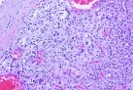

Figure 7.MEN1 syndrome denominating a pancreatic neuroendocrine neoplasm with accumulation of benign, adenomatous glands15.